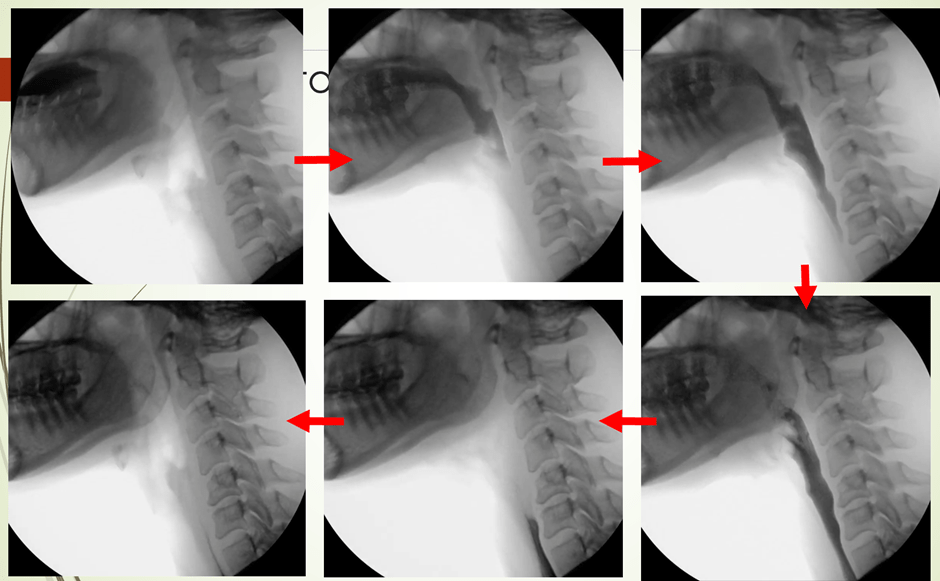

The following are some of the slides from the VFS workshop:

VFS: AnatomyVFS: The normal swallowing sequenceVFS: Case Study on the “Tennis Player” A chronic severe dysphagia client was successfully treated with therapy using sEMG biofeedback. This client managed to resume a regular diet and thin fluids and had his PEG tube removed.